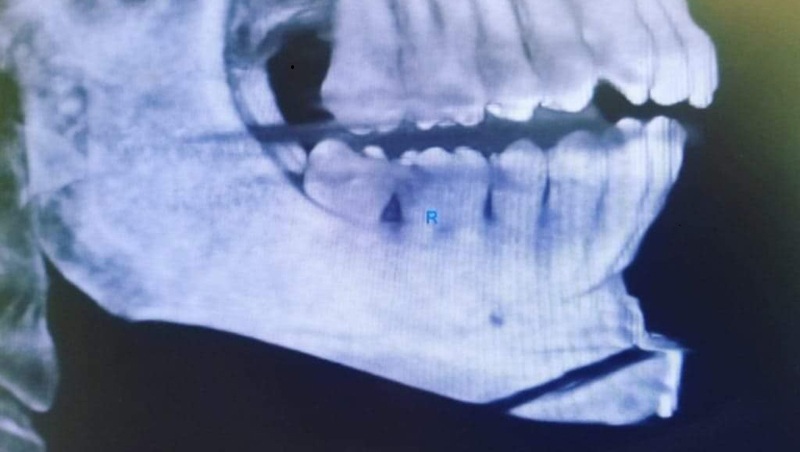

Lógicamente para que un paciente sea candidato necesita ser evaluado por un grupo de Especialistas que harán preguntas, examinarán y solicitaran un grupo de exámenes para definir que anomalia tiene el mentón para escoger la técnica quirúrgica.

El procedimiento implica hacer un abordaje intra o extra oral , es decir, una incisión que nos permita llegar al hueso de la barbilla, realizar unos cortes en la misma, quitar o añadir una porción de hueso, remodelar, centralizar y en algunos casos colocar un implante de silicona para aumenta la proyección de la barbilla.